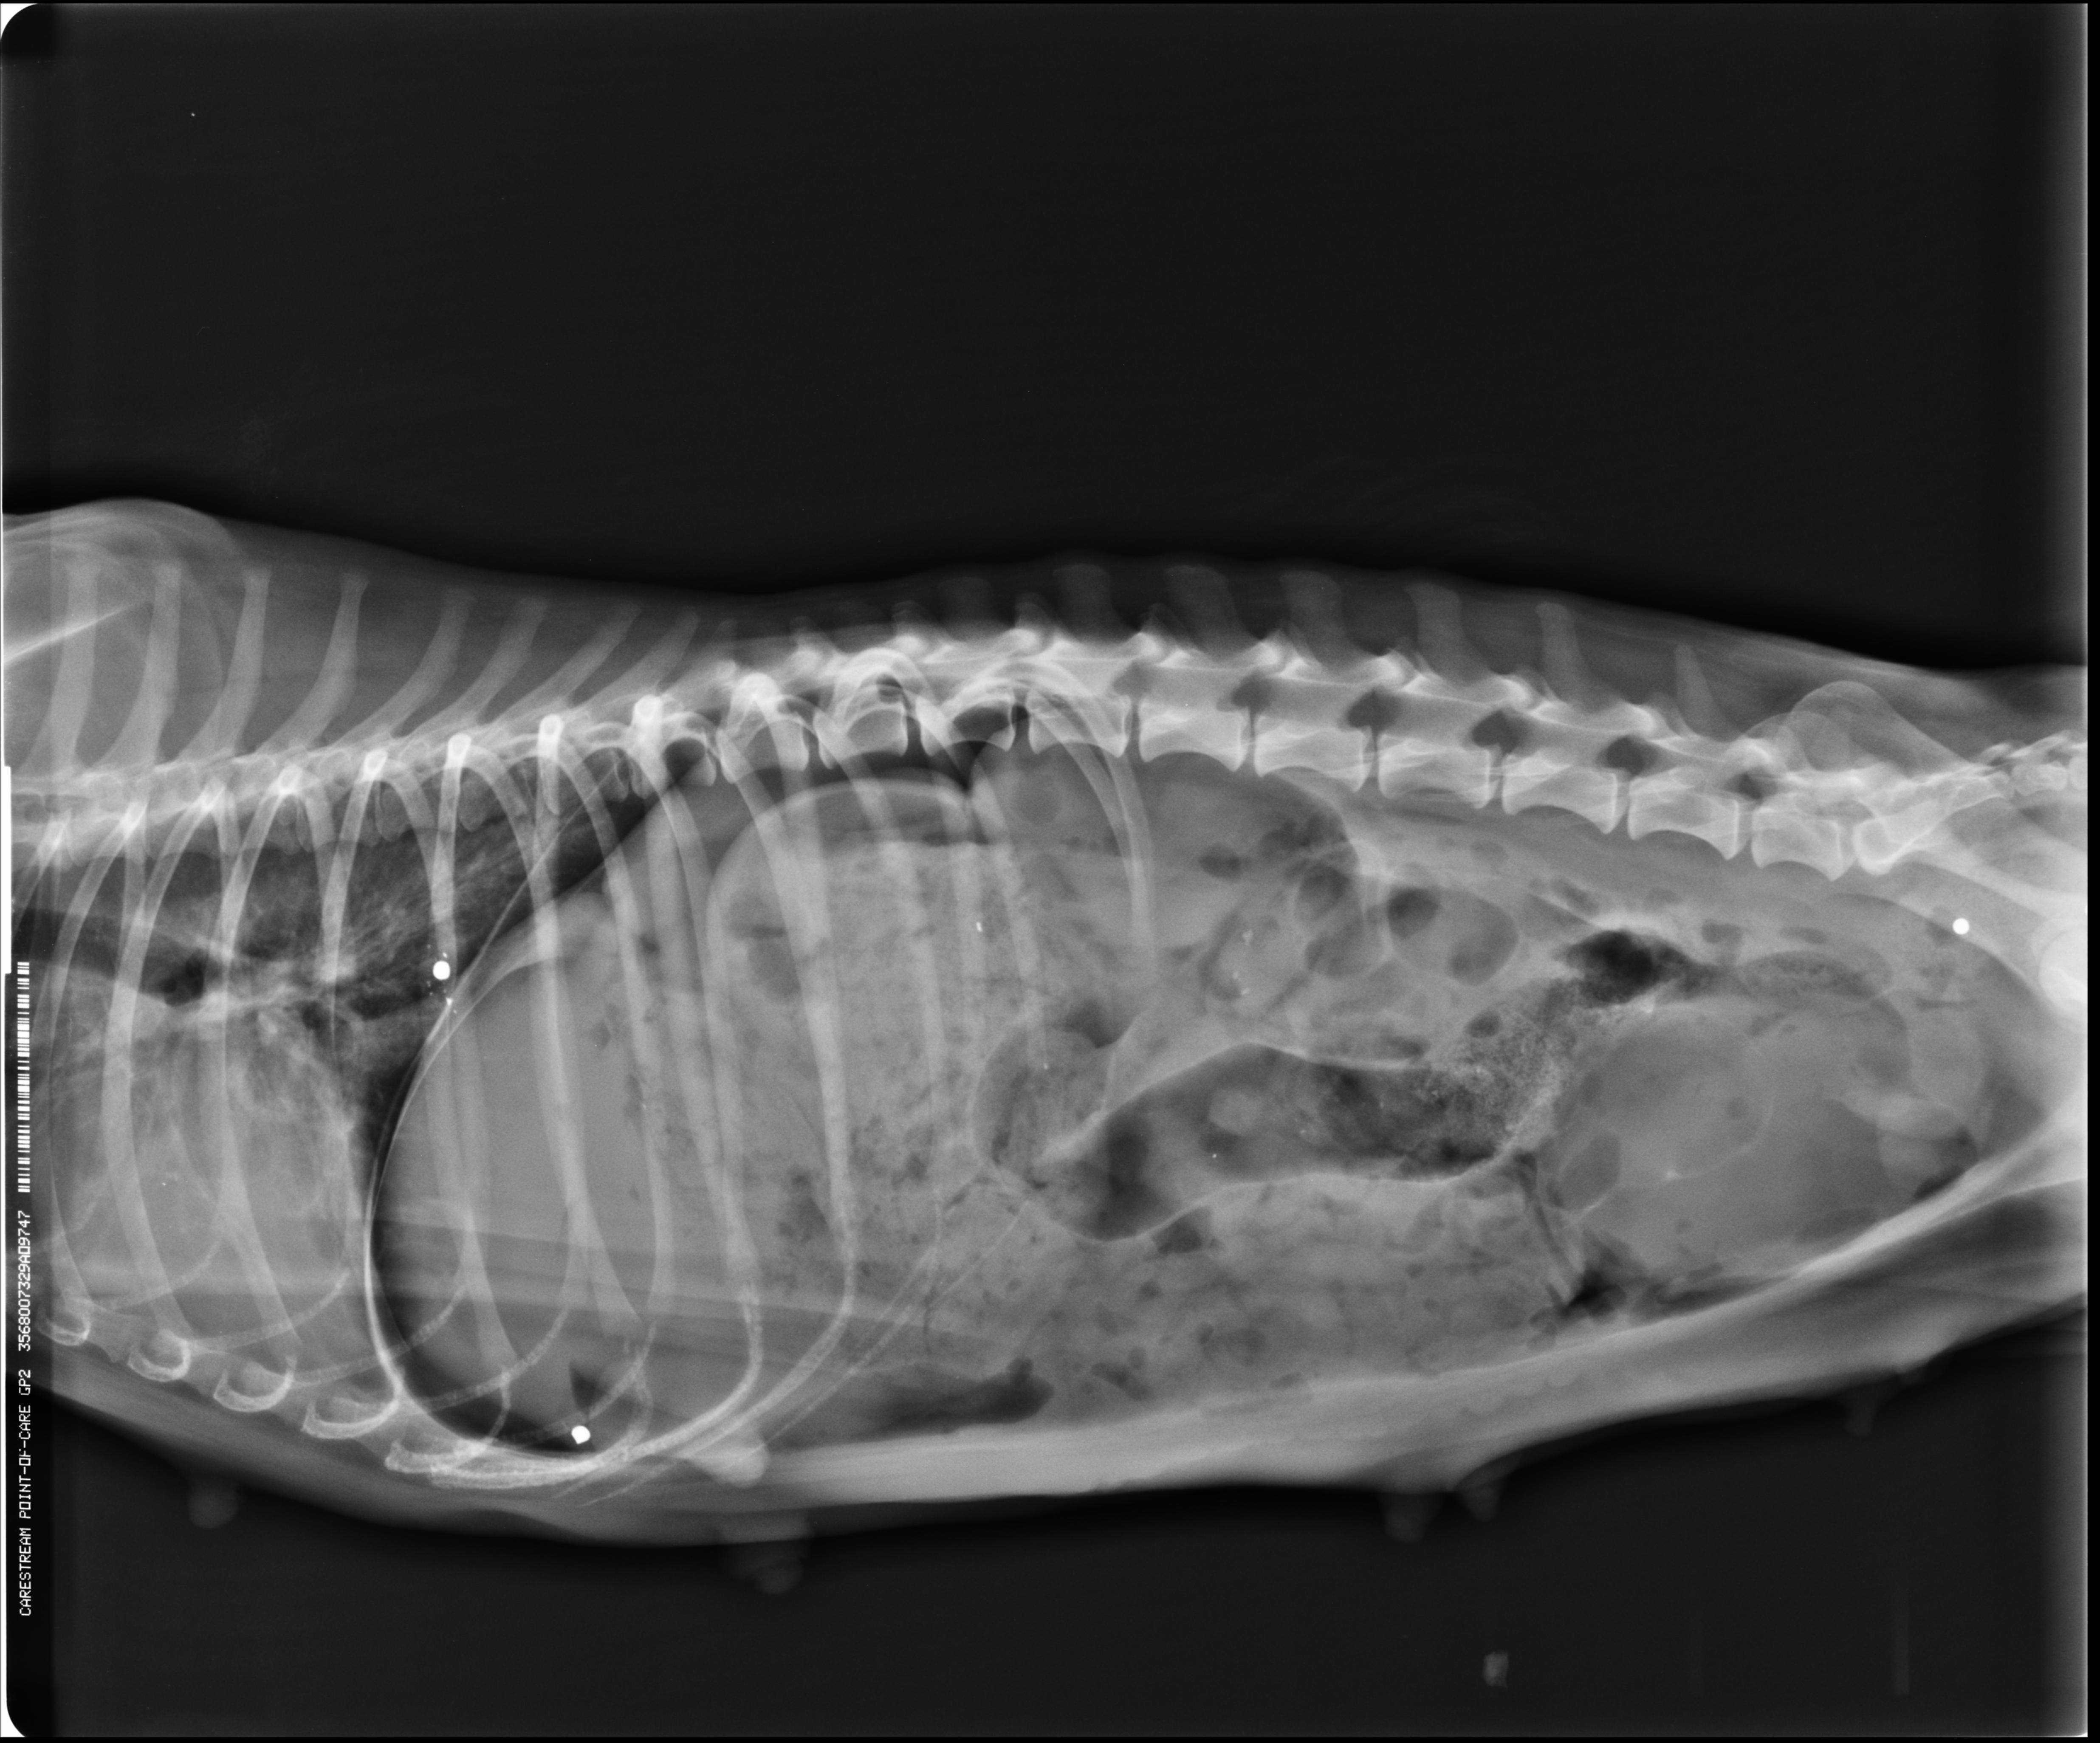

Vistas ventrodorsal y lateral en radiografía del mismo neumoperitoneo. la presencia de aire aumenta el contraste en radiografía por consiguiente se aprecia con claridad el borde craneal hepático. El diafragma también es gracias a la presencia de aire (color negro en las Rx).